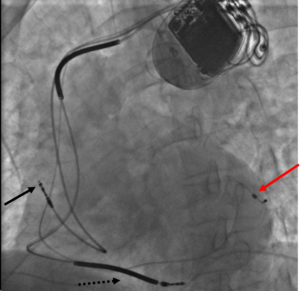

إن معظم منظمات ضربات القلب تركب في الجزء الأعلى من الصدر من خلال عملية تستغرق حوالي ساعة واحدة تجرى تحت تأثير التخدير الموضعي فقط، حيث يقوم الطبيب المختص بعمل فتحة صغيرة في الجلد ومن ثم يتم إدخال المنظم تحت الجلد بعد إتمام عملية توصيل السلك الكهربائي في المكان الخاص به بالقلب عن طريق الأوردة ومن ثـم يتـم إغلاق هذه الفتحة بالخيوط الجراحية.

وأثناء عملية التركيب هذه يقوم الطبيب بمراقبة حركة السلك من خلال شاشة تلفزيونية تحت الأشعة السينية لوضع السلك الكهربائي في مكانه المحدد بالقلب.